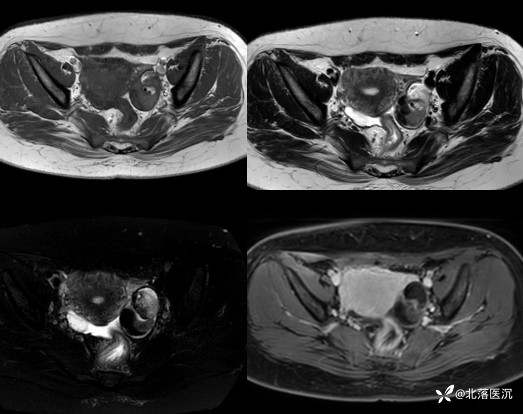

MRI表现:单囊或多囊的含脂肿块,大多包膜完整,病变内脂肪成分表现为T1WI、T2WI高信号影,脂肪抑制序列呈低信号改变;头发、牙齿及骨骼在各序列均为低信号改变;头结节信号表现多样,与头结节内含有多胚层结构有关

增强扫描:实性部分多无明显强化